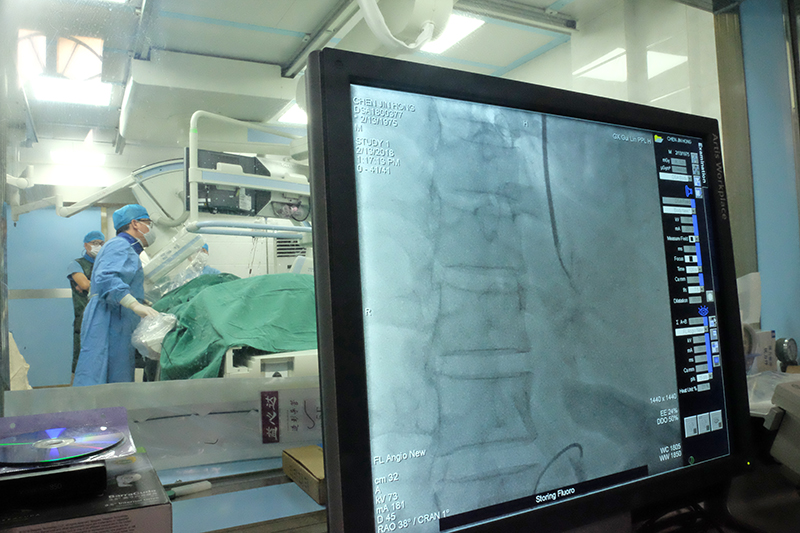

专家在为陈先生实施手术

为解决患者目前的危急病情,消化内科联系了自治区人民医院血管外科主任余雷会诊,在市人民医院血管外科主任黄弘伟团队协助下,为患者实施了TIPS手术,从患者的脖子穿刺颈静脉,在肝脏内人为打通一个通路(支架),从而降低门静脉的血流压力。经过一个多小时的紧张手术,患者的生命得到挽救。

医院专业的介入团队和先进设备为手术实施提供了有力支撑